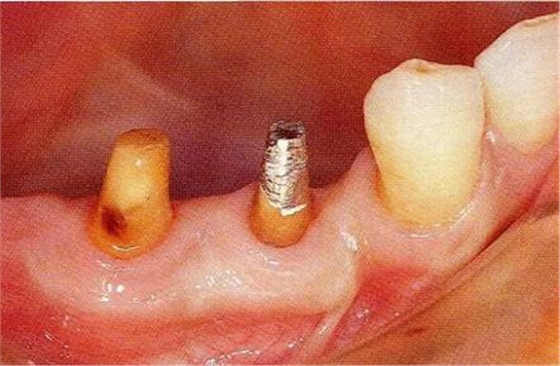

圖17-3▲拔牙的同時(shí)做骨外科處理,讓殘留的骨可以盡量平坦化。為了獲得頰側(cè)的附著齦,采用了游離齦瓣的處理。

圖17-4(左),5 (右)▲術(shù)后9年的口腔內(nèi)照片和X線片,牙槽嵴平坦化,牙周探診數(shù)值很小。